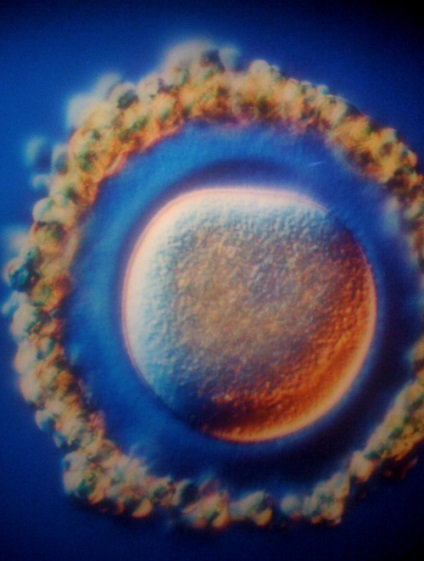

Sperma in trompa uterina se îndreaptă spre ovulului

Una dintre cele 200 de milioane de sperma paternă a pătruns prin coajă de ou